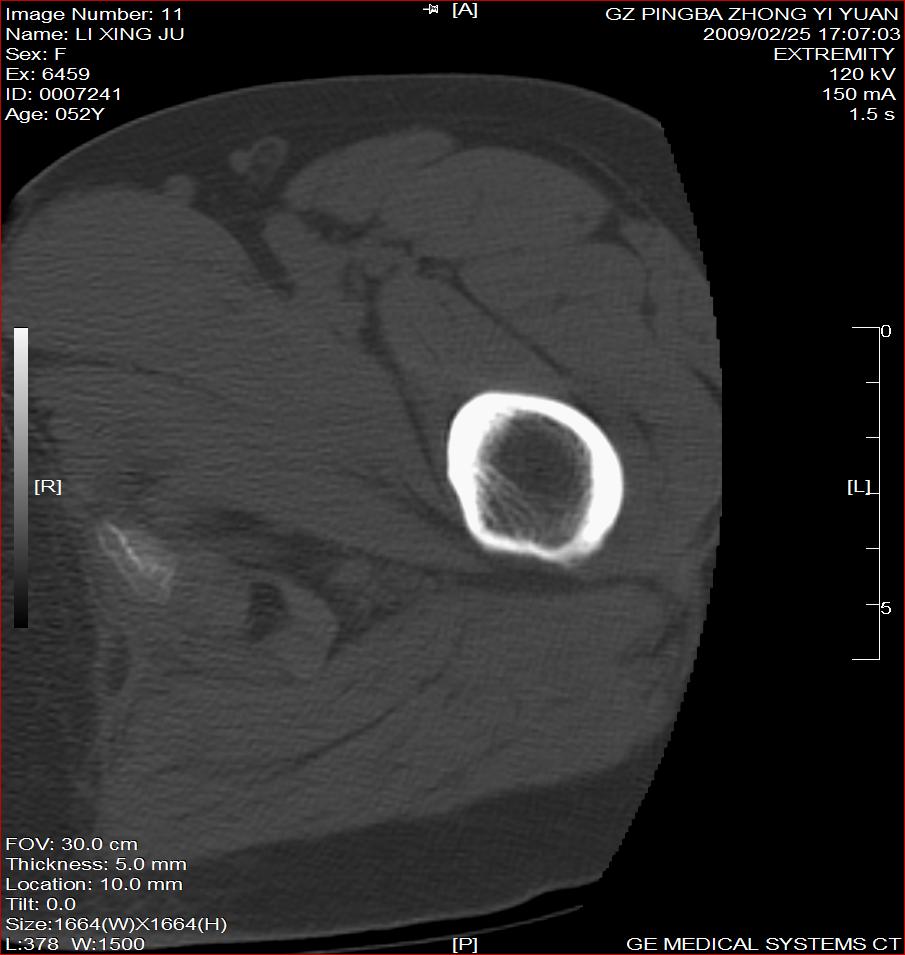

标题: CT18521:左大腿疼痛不适1+月 [打印本页]

标题: CT18521:左大腿疼痛不适1+月

考虑-----股骨骨化性纤维瘤可能性大,不除外---局限性骨纤

考虑:左股骨骨化性纤维瘤

考虑:骨纤或骨梗可能性大

考虑 左股骨骨化性纤维瘤。

骨梗塞

考虑骨化性纤维瘤可能性大